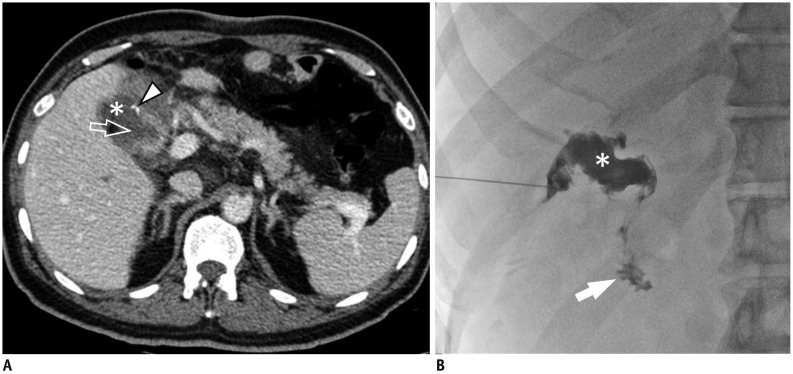

Fig. 8. Duodenal stump leakage.

60-year-old male patient underwent subtotal gastrectomy with Billroth II anastomosis.

A. On CT for postoperative fever evaluation, small fluid collection (*) is noted around duodenal stump with defect (open arrow) at lateral wall. Tiny high attenuating structure abutting on duodenal stump is surgical material (arrowhead). B. Cavitogram during percutaneous drainage well demonstrates complicated fluid collection (*) communicating with duodenum (arrow).